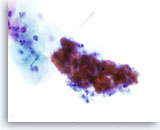

Lubricant D treated vial

…showing evidence of the lubricant present as a semi solid matrix resembling thin mucous. The lubricant stains a purplish hue in the background and is loosely associated with the epithelial cells. The cellularity is decreased as compared to the control. The lubricant effect in this case may not be as obvious to the observer.

10x

Lubricant D treated vial

…showing evidence of the lubricant present as a semi solid matrix resembling thin mucous. The lubricant stains a purplish hue in the background and is loosely associated with the epithelial cells. The cellularity is decreased as compared to the control. The lubricant effect in this case may not be as obvious to the observer.

10x